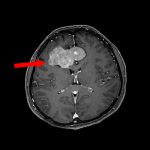

手術前2